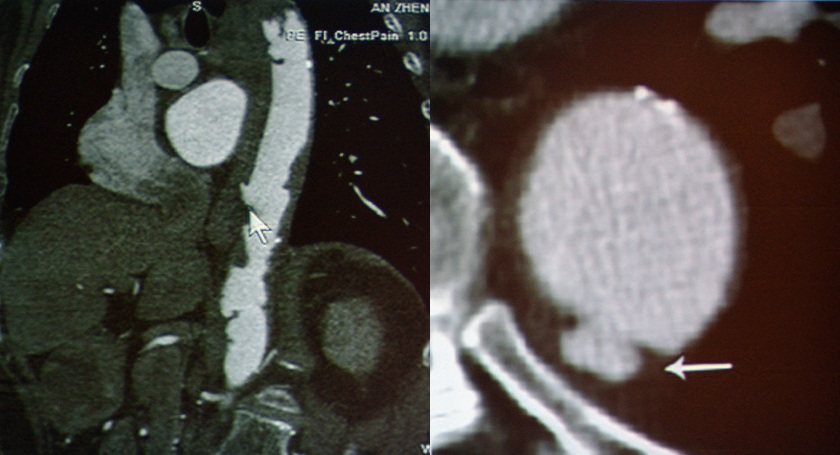

急性主动脉综合征:包括主动脉夹层、壁间血肿、穿透性溃疡。TRO可发现主动脉夹层的真假腔和内膜片。

图8 主动脉夹层Stanford A

图9 主动脉夹层Stanford B

图12 穿透性溃疡